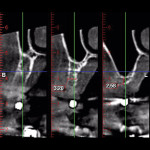

A 65-year-old woman had recently lost a fractured tooth No. 12, which was the anterior abutment for a fixed prosthesis extending to No. 15 (Figure 16). The CBCT cross-sectionals revealed a vertical and horizontal bone deficiency at No. 12, a narrowed ridge at site No. 13, and 2 mm of subantral bone at site No. 14 (Figure 17). The patient was informed she would need vertical and horizontal augmentation as well as sinus elevation prior to implant placement at site Nos. 12, 13, and 14.

Five months later, the CBCT revealed substantial horizontal and vertical augmentation along the entire extent of the ridge (Figure 20), thus permitting placement of three bone-level 4.1-mm x 10-mm implants (Straumann, www.straumann.us) (Figure 21). The implants were submerged and allowed to heal for an additional 4 months prior to uncovering and restoration (Figure 22 and Figure 23).